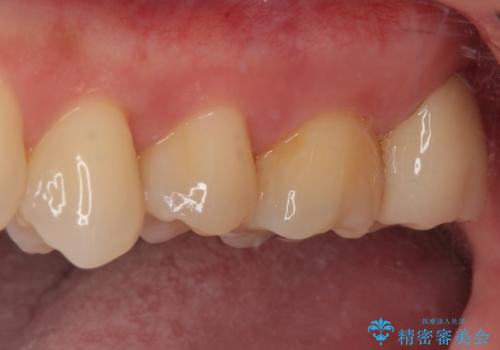

矯正治療で移動を終えた歯 オールセラミッククラウンでのむし歯治療

矯正治療により処置が可能な位置に歯が移動したため、オールセラミッククラウンにて補綴治療を行うこととしました。

セラミッククラウンの適合はレントゲン写真からも分かる通り、境界がぴったりと合った、高適合のものとなりました。